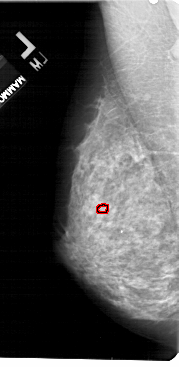

FILE: A_1755_1.LEFT_CC.OVERLAY

TOTAL_ABNORMALITIES 1

ABNORMALITY 1

LESION_TYPE CALCIFICATION TYPE PLEOMORPHIC DISTRIBUTION CLUSTERED

ASSESSMENT 4

SUBTLETY 1

PATHOLOGY BENIGN

TOTAL_OUTLINES 1

BOUNDARY